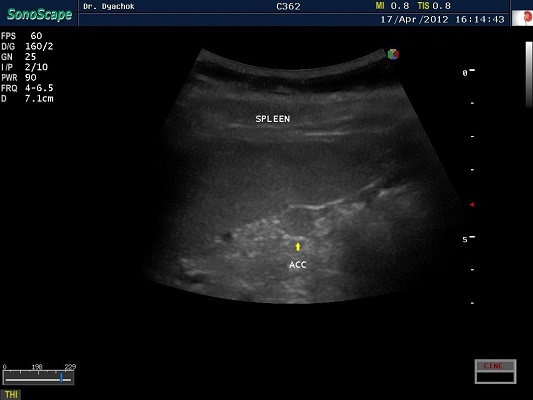

SonoScape S2N Vet – уникальная узи-система, выполненная в виде портативного ноутбука для легкой переноски. Отличается эта система цветным форматом визуализации, а также крайне чувствительными доплеровскими режимами, работающими на уровне премиальных аппаратов. При оптимальной цене – это очень хорошее и сбалансированное решение для ветеринарной клиники.

Диагональ монитора составляет 15,6 дюймов, что обеспечит комфортную работу для врачей и полный спектр визуализации для пациентов. Компактный вес не превышает 5 кг. (вместе с батареей), что оценят выездные бригады скорой помощи или ветеринары, выезжающие на дом.

Цифровая рабочая станция S2N Vet предполагает наличие жесткого диска для записи данных, составление и экспорт отчетов с возможностью добавления изображений, ведение базы данных пациентов.

Данный аппарат является незаменимым помощником в диагностической медицине. Ему нет конкурентов по оснащению, компактности и цене, а значит пора сделать правильный выбор для вашей клиники.